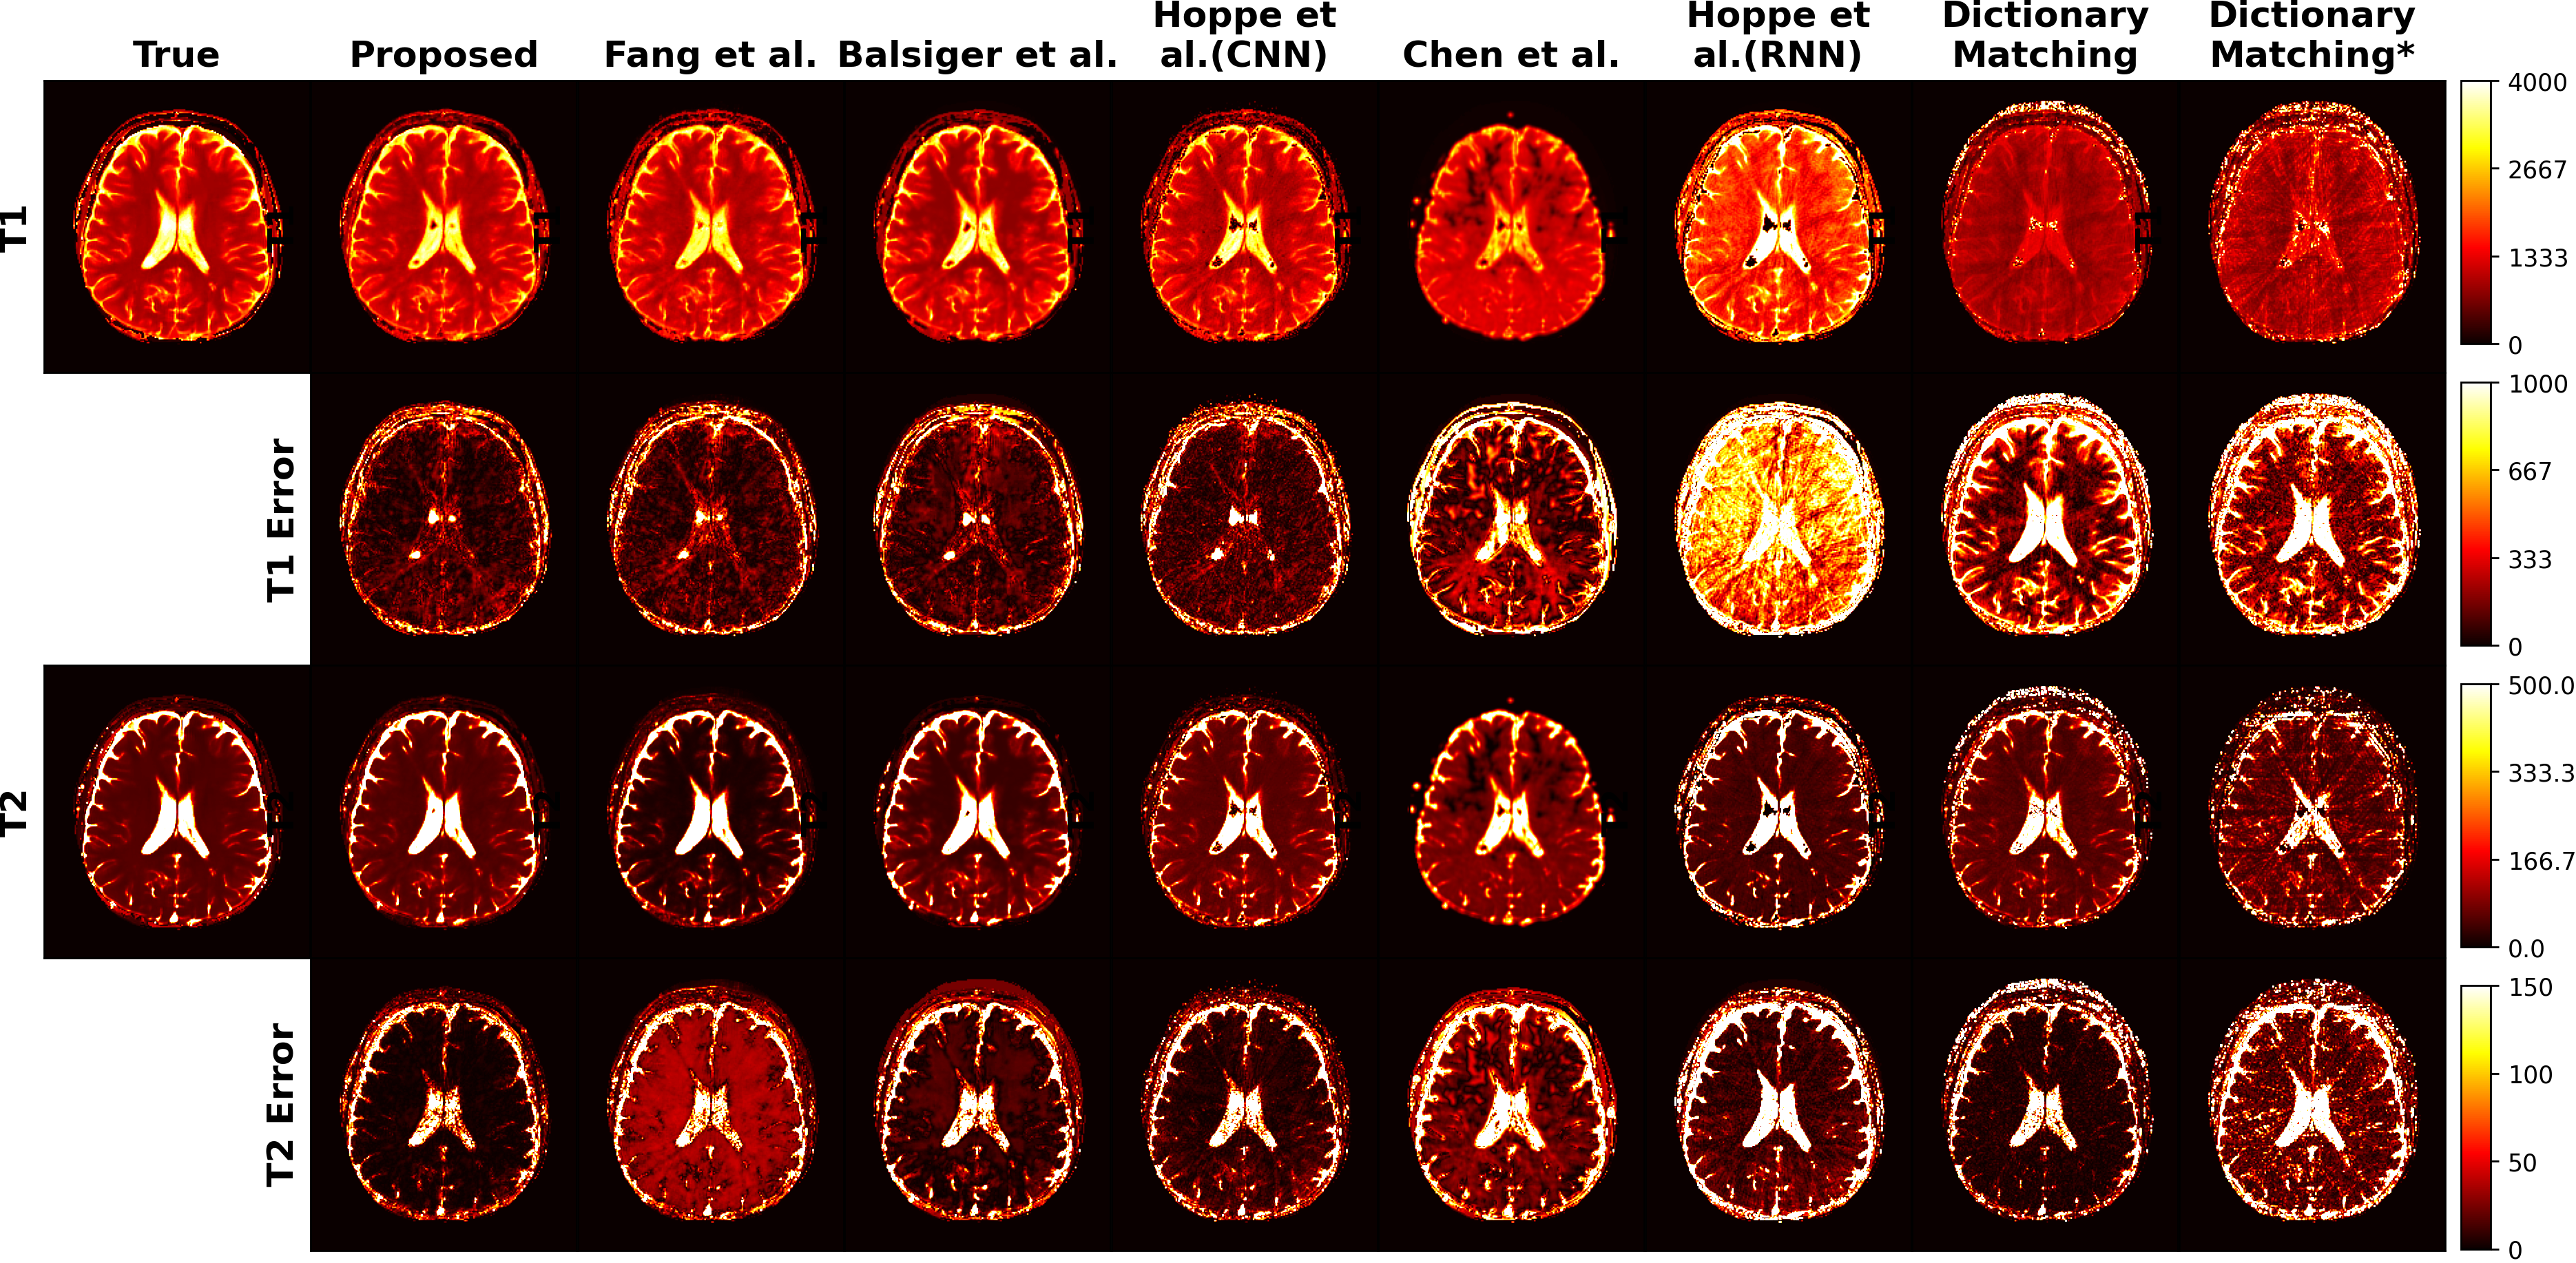

Refer to caption

Figure 5: Proposed model to state-of-the-art methods compared qualitatively by testing on a test subject. T1 and T2 errors are the mean absolute differences as shown in Eq.(3) between reconstructed parameters and true parameters in ms. Backgrounds of reconstructed images are masked to highlight interested region and errors in Table I are calculated accordingly. *SVD was used for channel reduction from 2000 to 5 in pre-processing for Dictionary Matching.

TABLE I: Comparisons of proposed model with a variety of available techniques where errors are calculated between ground truth images and background-masked reconstructed images as shown in Figure 5 by using Mean Absolute Error (MAE) in percentage. *SVD is used for channel reduction from 2000 to 5 in pre-processing for Dictionary Matching.

Models T1 - MAE(%) T2 - MAE(%)

Dictionary Matching 4 1.01

Dictionary Matching* 4.7 1.96

Hoppe et al.[12] (RNN) 5.61 1.79

Chen et al.[16] 3.38 1.3

Hoppe et al.[18] (CNN) 2.07 1.03

Balsiger et al.[13] 1.82 1

Fang et al.[15] 1.72 1.14

Proposed 1.58 0.57

The qualitative results presented in Fig. 5 visually demonstrate the reconstruction performances of the proposed model and the models in comparison for the T1 and T2 parameters. The rows marked as T1 and T2 (1st and 3rd rows, respectively), show the reconstructed tissue parameters by the models. T1 error and T2 error images (2nd and 4th rows, respectively) show the differences between the reconstructed and the true tissue parameters. These qualitative results further support that the proposed model achieves the best performance visually for the reconstruction of T1 and T2 tissue parameters.